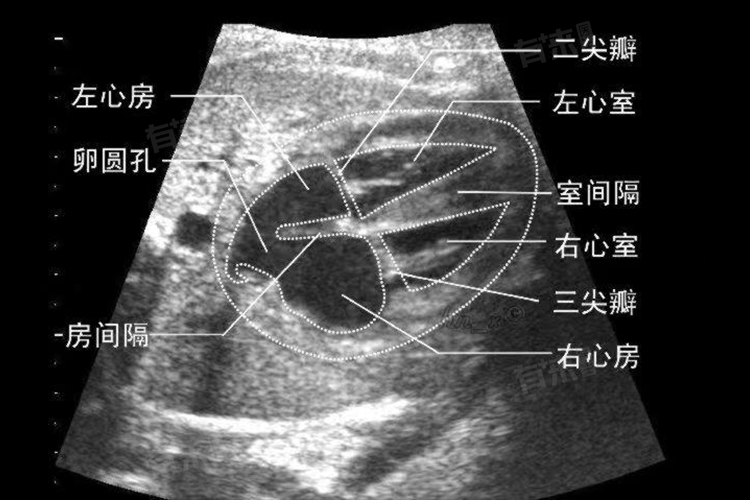

- 常规的经胸心脏超声检查,是最基础的心脏超声项目,费用通常处于价格区间的下限。医生将超声探头放置在胸部,从多个角度获取心脏图像,观察心脏的大小、形态、室壁厚度、瓣膜结构与功能、心腔内血流情况等。这种检查操作相对简便,对设备和技术的要求处于基础水平,因此费用相对较低。其能够初步筛查心脏是否存在先天性结构异常、瓣膜疾并心肌病等常见问题,是临床广泛应用的检查方式。